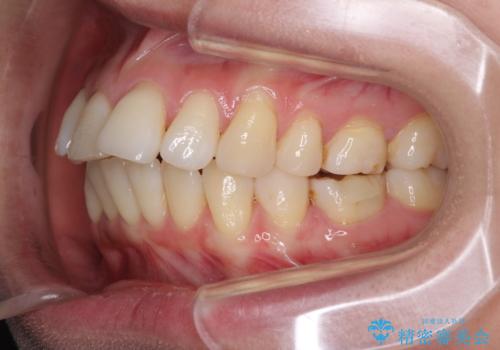

- 上の前歯の出っ歯を治したいとのことで来院された患者様です。

後戻りによる再矯正というもともあり、インビザラインを希望されていました。

上顎の歯は後方移動とIPR(歯と歯の間を削る)によって口元が引っ込むように、下顎は歯列全体の拡大とIPRによって上顎とバランスよく咬み合うように設計し、インビザラインにより治療を行うこととしました。